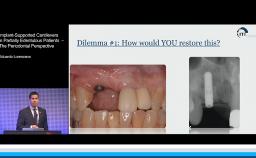

Implant-Supported Cantilevers in Partially Edentulous Patients – Pros Perspective

This lecture considers the incorporation of cantilever extensions into implant-supported prostheses as a viable option in situations where local conditions of the residual edentulous ridge preclude the possibility of placing an implant. The literature presented in this lecture substantially supports the conclusion that the incorporation of single cantilevers into implant-supported prostheses does not have a significant effect on the amount of peri-implant marginal bone loss. Literature also suggests that implant-supported fixed prostheses with crown-to-implant ratios greater than 1:2 do not correlate positively with marginal bone loss. This presentation also discusses fixed implant rehabilitations with multiple cantilevers in edentulous patients, showing that implant number and distribution along the edentulous ridge seem to influence the prosthodontic survival rates only in the maxilla.

- recognize the indications for single cantilevers in implant-supported prostheses